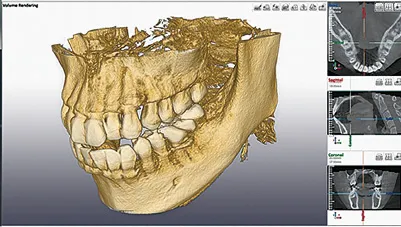

微細かつ複雑な根管形態に対し、CTによる三次元的な解析と、マイクロスコープの拡大視野下での処置を導入。これにより、感染源の見逃しリスクを最小限に抑えます。

CT撮影を行うことにより、従来の2次元のレントゲン写真と比べ、これらを立体的に確認することができます。診断の精度向上に有効なツールです。

レントゲンやCTで歯の状態を正確に診断

むし歯や炎症の進行度、根管の形状などを把握するために、レントゲンやCT撮影を行います。検査結果をもとに、根管治療が必要かどうか、治療期間や費用について丁寧にご説明します。

| 補足事項 | 【診断のポイント】 CT画像にて頬側の骨吸収が確認されましたが、他部位に歯周病がないことや未処置歯(イニシャルトリートメント)であることを踏まえ、 根管治療による骨再生が可能と判断されています。 【経過】 術後1週間でフィステル(瘻孔)が消失し、9ヶ月後にはレントゲン上で骨の完全な再生が確認されました。 |